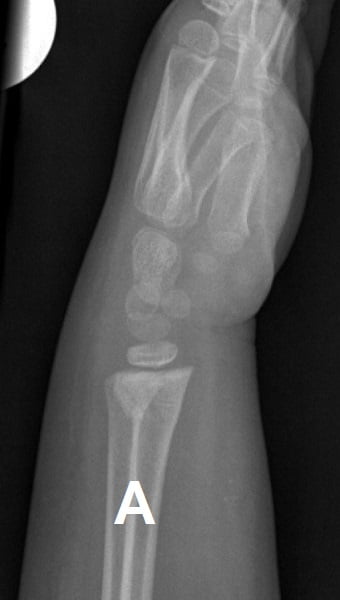

Figure 1: Buckle Fracture of the Distal Radius

Buckle fractures of the distal radius represent about 50% of pediatric fractures of the wrist.1

The cosmetic and functional prognosis of this fracture is excellent even if it associated with an ulnar buckle/styloid fracture.2,3 Data from eight randomized control trials conducted in the UK, Canada and the US has demonstrated that treatment with a removable splint is at least as effective as a short arm cast with respect to recovery of physical function.4 Further, these RCT’s demonstrated that parents and families preferred the removable splint, and splinting was found to be more cost-effective for the health care system.